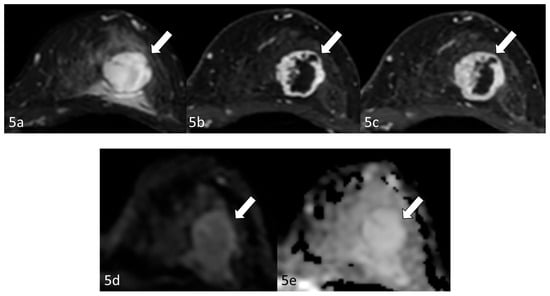

Radiological examination after 11 years: Screening mammography showed a newly visible dense, ill-defined mass in the upper outer quadrant of the left breast (Figure 3). Ultrasound demonstrated a 27 mm oval hypoechoic mass with central low and peripheral iso-to-hyperechoic areas and posterior enhancement (Figure 4a,b). Color Doppler imaging revealed abundant peripheral vascularity (Figure 4c). Strain elastography showed mildly reduced strain (Figure 4d). On MRI, a well-circumscribed round mass with high signal intensity was observed on fat-suppressed T2-weighted images (Figure 5a). Dynamic contrast-enhanced imaging demonstrated spatially heterogeneous enhancement spreading from the periphery to the center, with a fast-plateau enhancement pattern in the peripheral portion and a medium persistent enhancement pattern in the central portion (Figure 5b,c). The mass showed high signal intensity on diffusion-weighted imaging and high apparent diffusion coefficient (ADC) values (Figure 5d,e). The mass was classified as Breast Imaging Reporting and Data System category 4B, and ultrasound-guided vacuum-assisted biopsy was performed.

Figure 5. Magnetic resonance imaging (after 11 years): Magnetic resonance imaging (MRI) demonstrated a well-circumscribed round mass (arrow) with high signal intensity on fat-suppressed T2-weighted images (a). Dynamic contrast-enhanced imaging demonstrated spatially heterogeneous enhancement spreading from the periphery to the center, with a fast-plateau enhancement pattern in the peripheral portion and a medium persistent enhancement pattern in the central portion (b,c). The mass (arrows) showed high signal intensity on diffusion-weighted imaging and a high apparent diffusion coefficient value (d,e).